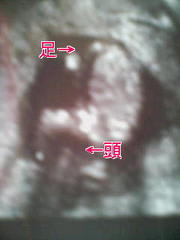

検診日

今日は4ヶ月の検診日。 もうお腹の子と過ごして4ヶ月もたったんだぁ。早いね。 半年後には産まれちゃうんだ! だいすけパパ、準備は大丈夫!? ボーロばかり食べて、お昼寝ばっかりしてる場合じゃないよ!! 赤ちゃんは頭から足ま […] 続きを読む »